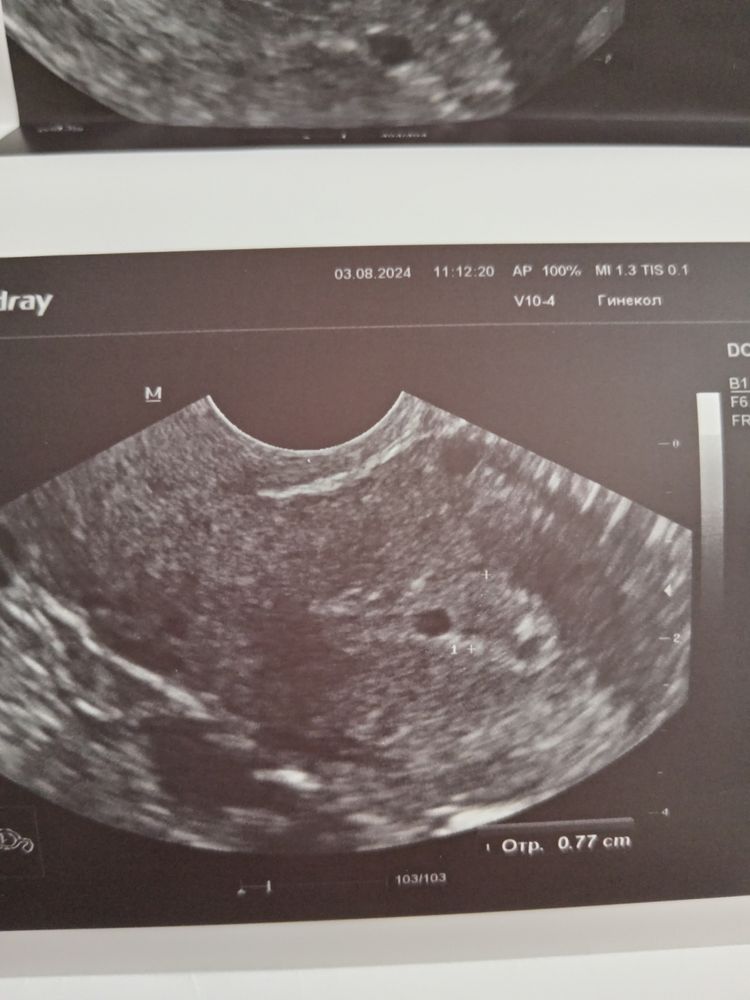

УЗИ 12 дц, анэхогенное включение

Результаты УЗИ

Девочки, может кто сталкивался? В полости матки анэхогенное включение 3.8 мм. Сейчас нахожусь в криопротоколе, жду О, на 5 день перенос. Врач видела УЗИ, значение не предала этому. А я переживаю стоит ли переносить с этим непонятным включением? На 3 дц все чисто было